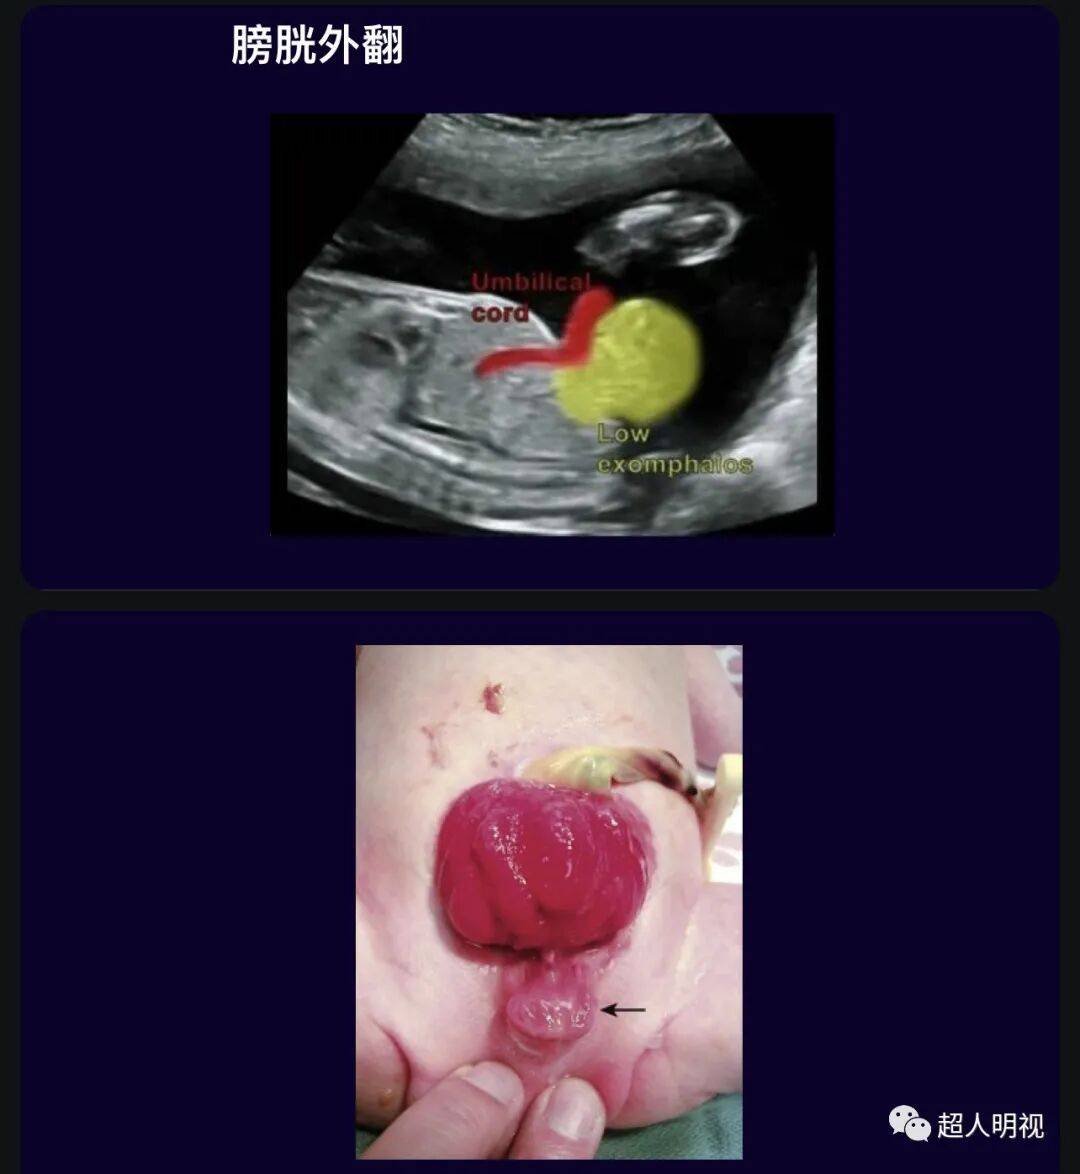

❷膀胱外翻: 以膀胱经腹壁前突为特征。它与下尿道畸形和其他泌尿畸形有关。

膀胱外翻四大超声表现:

1) 胎儿的盆腔内末见膀胱

2)下腹部腹壁有包块凸出

3)肾脏正常,羊水量正常

4)胎儿性别很难确定